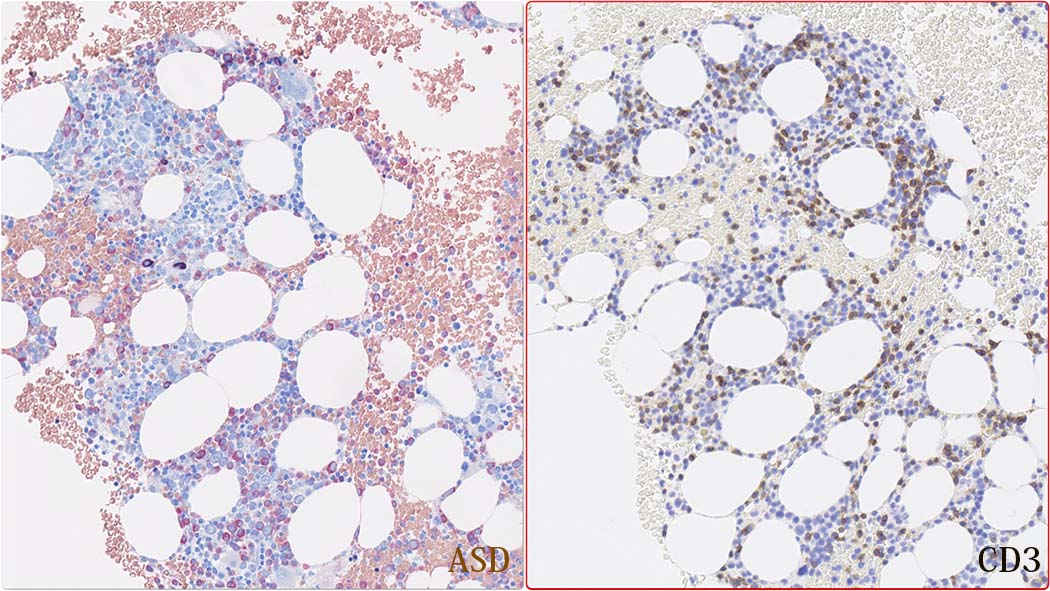

Bone marrow組織所見(clot section);

免疫染色

CD3とCD20

CD4, CD8とcytotoxic granulesの免疫染色

CD4陽性細胞の多くはマクロファージ. CD8+, toxic molecule+ のT-cellが増加している.本例では, TIA1陽性細胞が増加しているが, granzymeB陽性細胞はそれほど多くない.